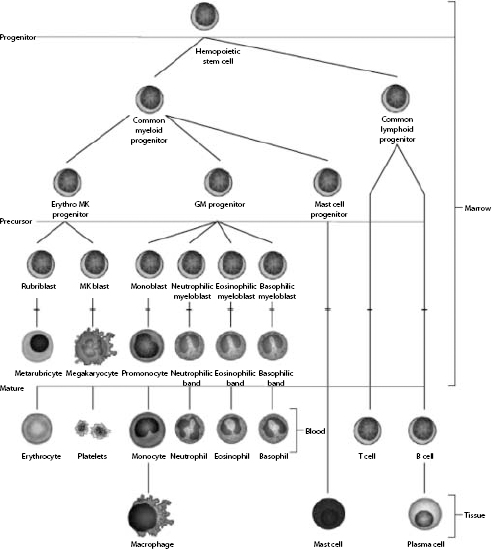

Hemopoietic stem cells have the ability to develop into common myeloid progenitors and common lymphoid progenitors (Fig. 1.1). Erythrocytes, megakaryocytes, and all leukocytes (except lymphocytes) are generated from common myeloid progenitors. The first level of committed differentiation to erythrocytes is within the precursor cell compartment. The bone marrow microenvironment provides the structural and biochemical support for normal hemopoiesis. Growth factors, transcription factors, adhesins, interleukins, and other mediators comprise a complex system that responds to increased demands when required and maintains a finely tuned balance under normal circumstances. The expression and availability of these factors influence the balance among the various committed lineages. Erythropoietin (EPO) is the most important growth factor for maintaining erythroid proliferation. If peripheral blood evaluation reveals an inadequate or unexplained bone marrow response, examination of the marrow is usually indicated.

Figure 1.1 The cells of the blood and lymphoid organs and their precursors in the bone marrow.